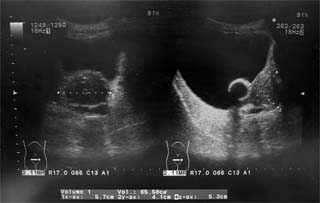

エコー

計測では前立腺サイズは65mlとなっていますが、幅も前後方向も少し大きくとりすぎていますので、もう少し小さいと思います。